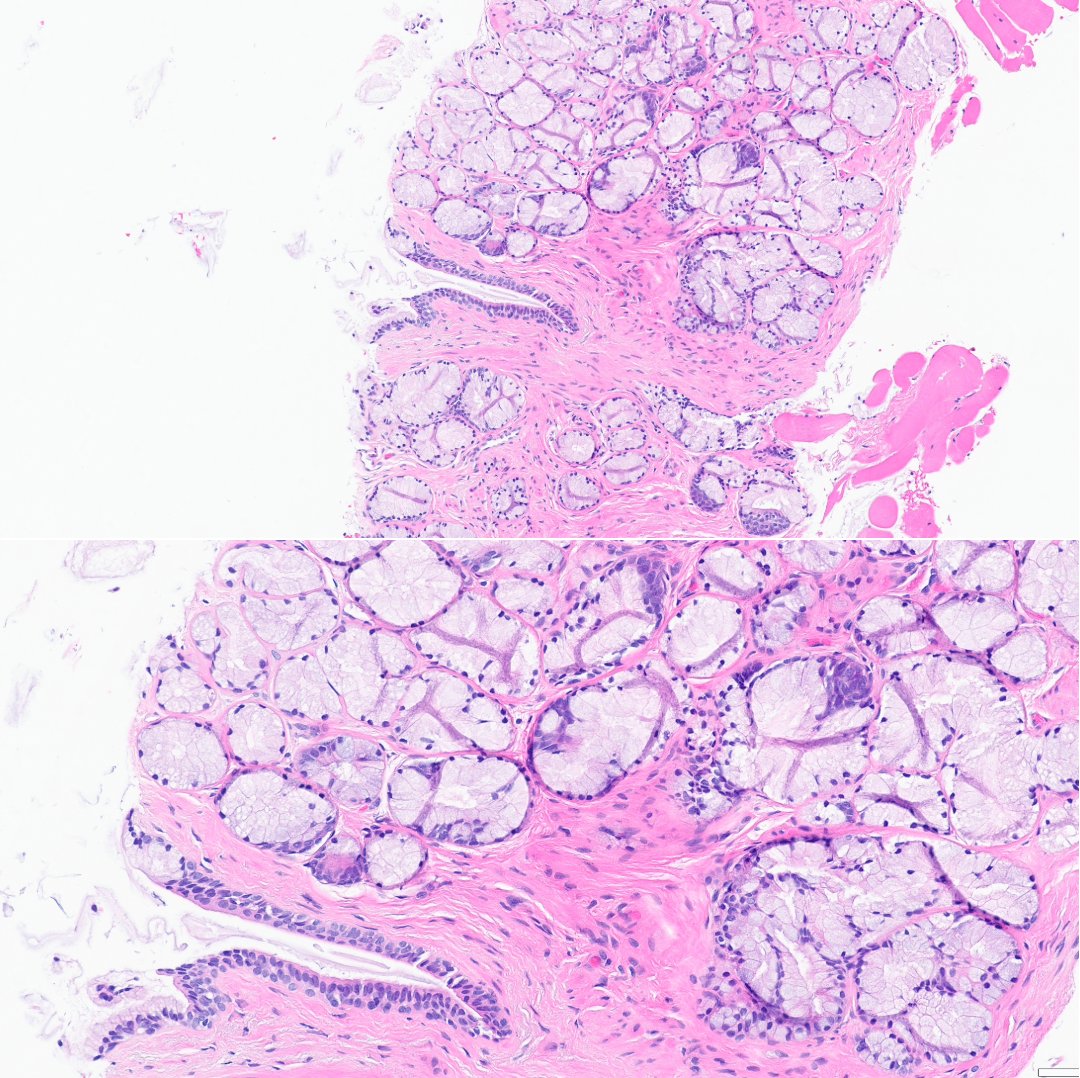

HER2 interpretation is increasingly complex—with evolving definitions come real challenges, especially reproducibility. We’ll cover navigating HER2-low & ultralow in a clinically meaningful way.